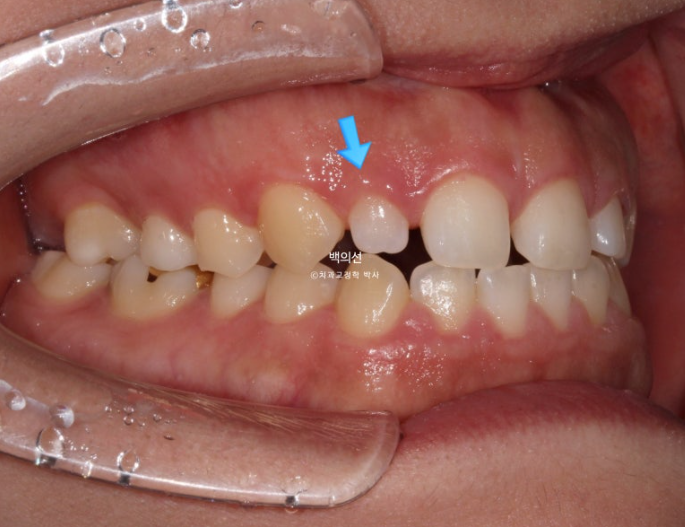

파란화살표는 왜소치 입니다.

교정 후 라미미네이트 수복이 필요합니다.

교합면에서 보면 안쪽 맨 뒤 큰어금니 하나가 없는 것이 보입니다.

선천적 결손치아 입니다.